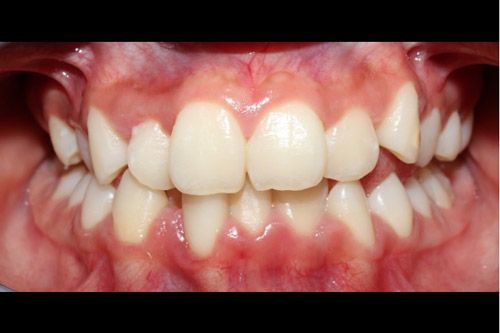

Paciente femenino de 15 años de edad que presenta una hipomineralización incisivo molar (HIM) de grado moderada código 2 y caries incipiente en el O.D. 23 en la cara vestibular. Se encuentra aparentemente sana sistémicamente.